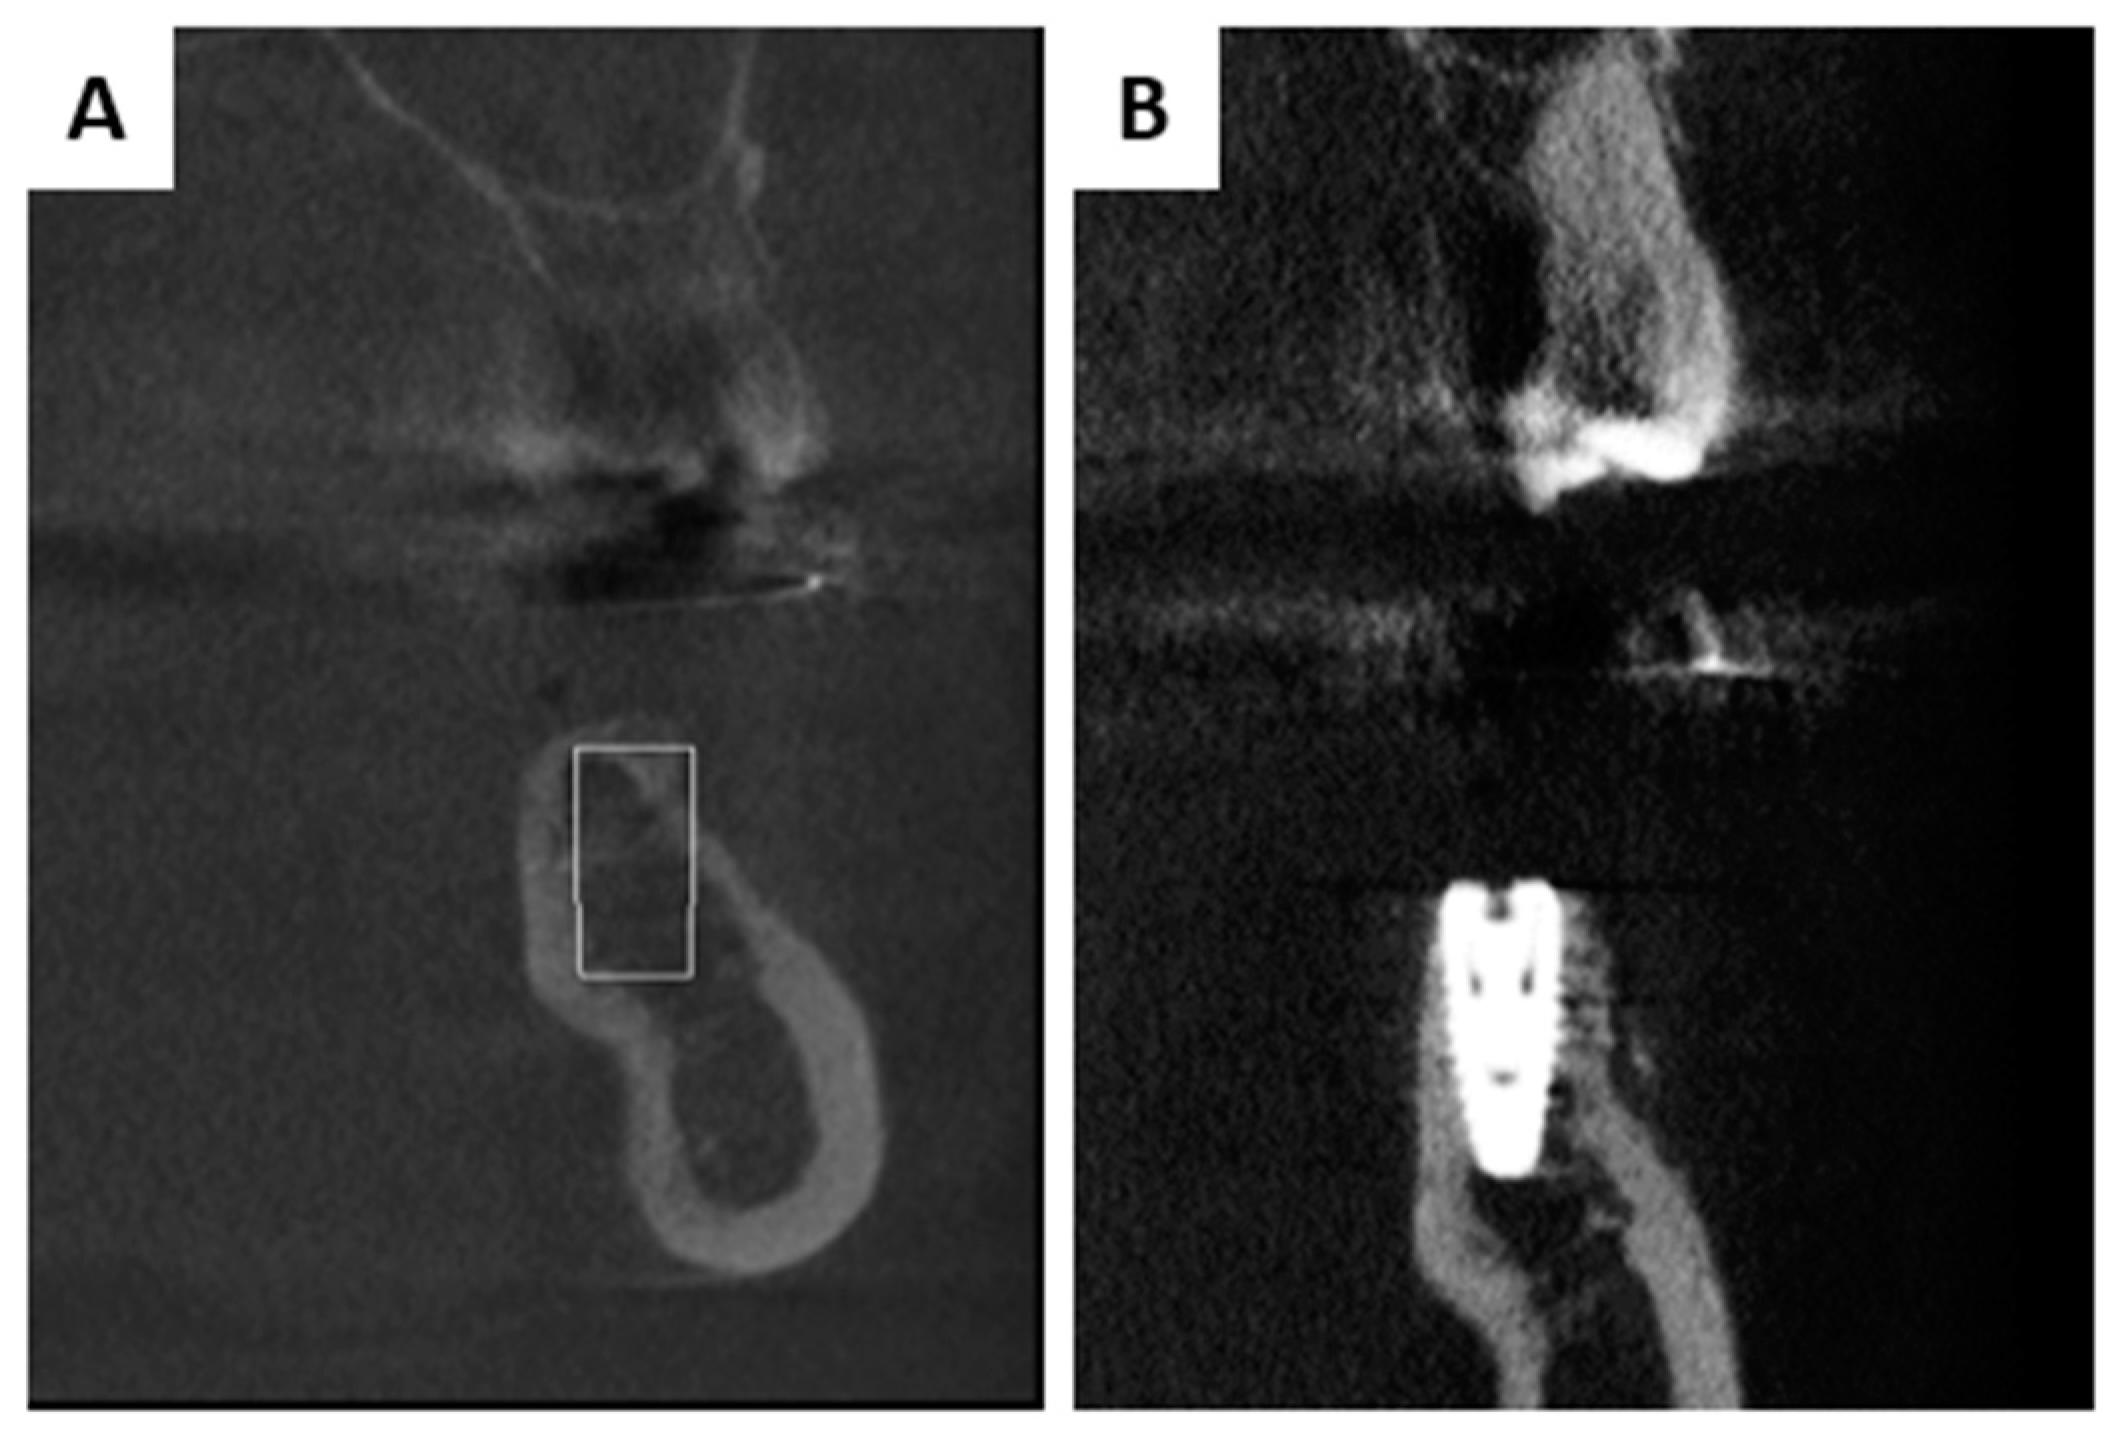

2.2. Interactions in Patients

3.2. Interactions in Patients